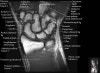

손목 관절의 MRI 단면 영상

- Coronal section

Coronal T1 imaging evaluates bone marrow signal (ex. increased in avascular necrosis) and the relationship of the osseous structures to each other (ex. scapholunate disassociation).